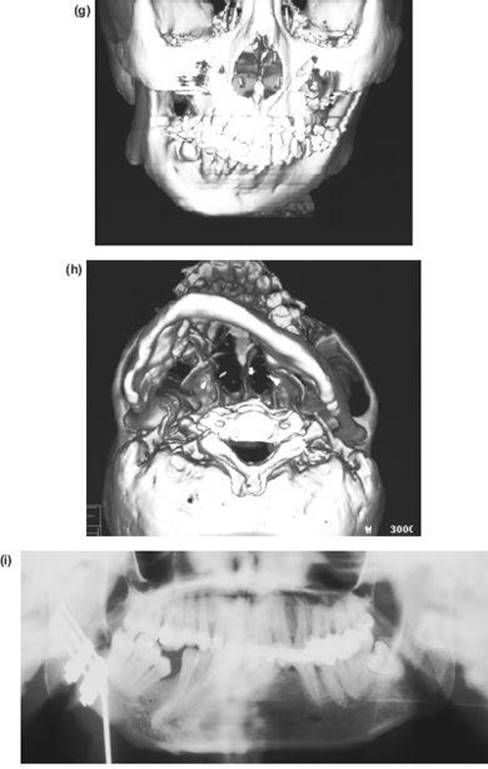

7. The nasal septum and pterygoid plates are separated intraorally, as in the Le Fort I operation.